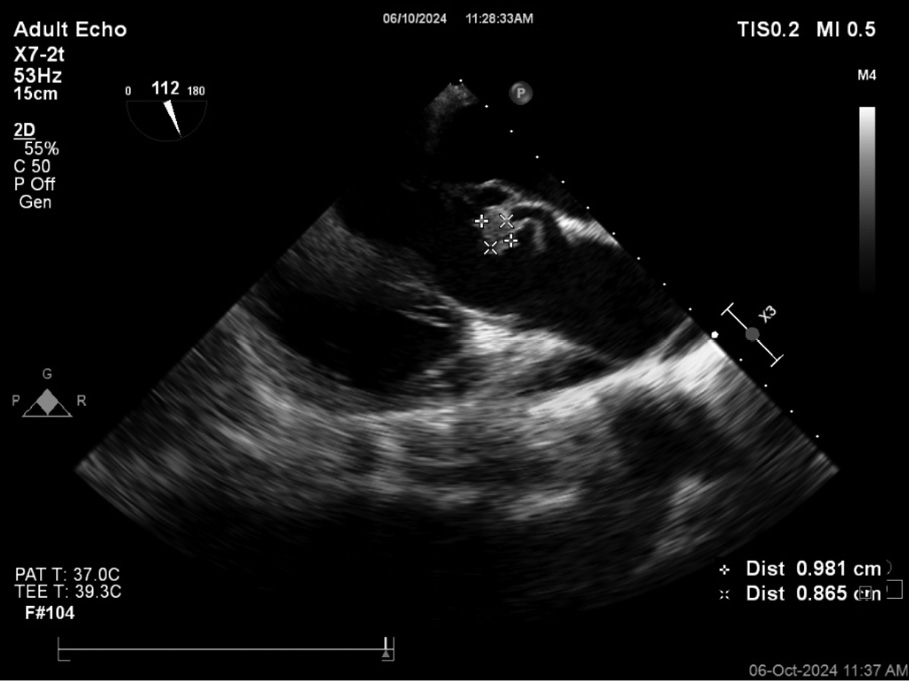

Three sets of blood cultures were obtained on admission, all of which were positive within one day showing growth of Granulicatella elegans. The blood culture was processed in BacT Alert system (Biomerieux Inc), Gram stain showed small spherical Gram-positive cocci in chains (Figure 1A), subculture showed growth of fine non hemolytic colonies and features of satellitism (Figure 1B). The organism was identified as Granulicatella elegans by VITEK 2 Compact System (Biomerieux Inc.) and it was susceptible to penicillin, ceftriaxone, erythromycin, levofloxacin, vancomycin, and linezolid. MRI of the brain showed an old infarct in the middle cerebral artery (MCA) territory, likely secondary to a prior embolic event. Transoesophageal echocardiography (TEE) revealed vegetations on a bicuspid aortic valve with mild aortic regurgitation (Figure 2).

Figure 2 - Transoesophageal echocardiography (TEE) revealed vegetations on a bicuspid aortic valve with mild aortic regurgitation.